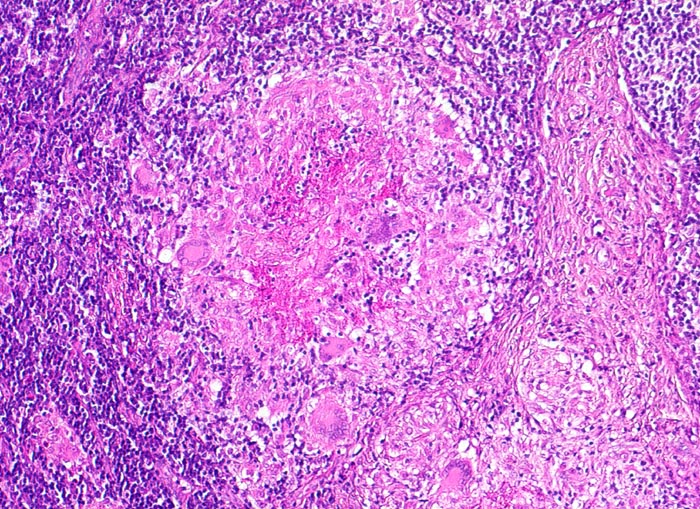

Basel 3BA HS/ Verkäsende Lymphknotentuberkulose

Verkäsende Lymphknotentuberkulose

• Lymphknoten mit ausgedehnten konfluierenden eosinophilen Nekrosezonen und nur wenig erhaltenem Lymphknotengewebe (blau).

• In den grösseren Nekrosearealen sind Kerntrümmer von neutrophilen Granulozyten erkennbar.

• Demarkierung der Nekroseareale durch schlanke Epitheloidzellen, Riesenzellen vom Langhanstyp mit hufeisenförmig angeordneten Kernen und Lymphozyten.